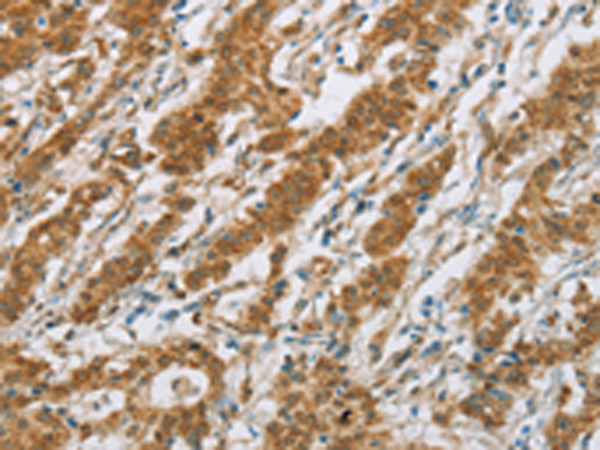

分类: 科研抗体货号: P08194别名: CPC9; CYP2C; CYP2C10; CYPIIC9; P450IIC9应用: IHC反应种属: Human